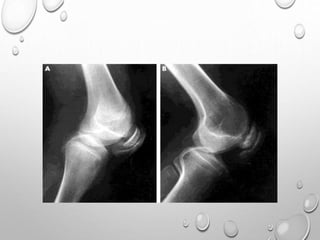

FLATTENED AND SQUARED-OFF EPIPHYSES

DOUBLE LAYERED PATELLA……PATHOGNMONIC

HYPOPLASTIC TIBIAL AND FEMORAL CONDYLES WITH SHALLOW

INTERCONDYLAR NOTCH

METAPHYSES ARE FLARED